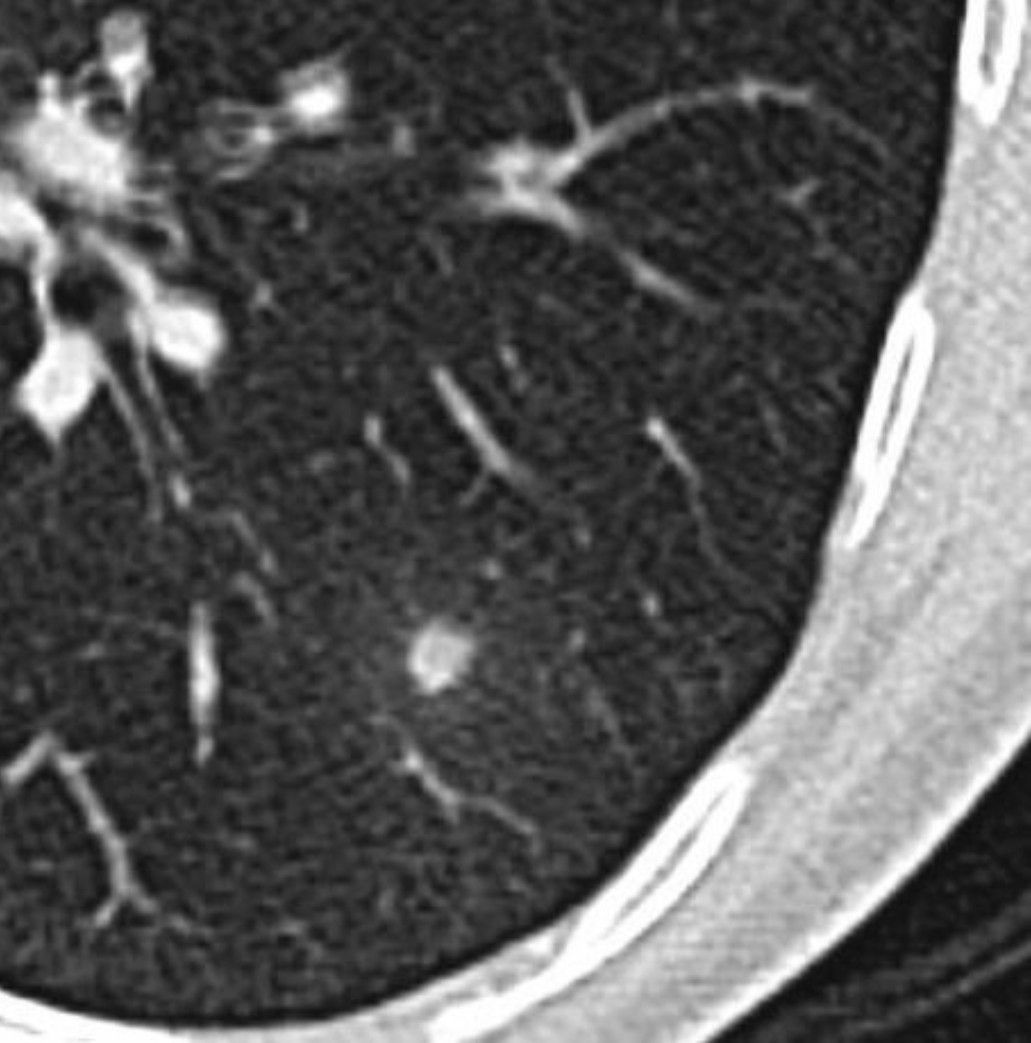

There is a 6 mm nodule in the left lower lobe, with faint surrounding ground glass attenuation, which is new compared with a CT chest from 5 months prior. The ground glass halo around a nodule suggests involvement of the adjacent alveoli or septa at a resolution too fine for our CT equipment... it could represent either fluid/hemorrhage or possible "lepidic" growth of a tumor (as with bronchoalveolar cell carcinoma).. By: https://www.instagram.com/p/C4-zEILN-4J/?utm_source=ig_web_copy_link